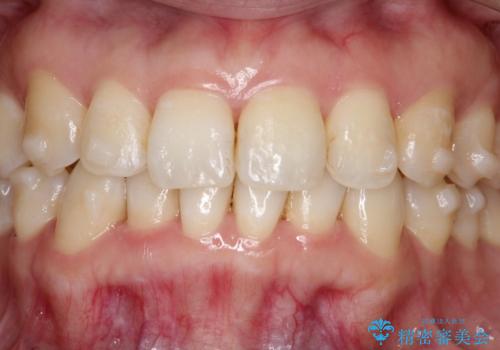

[エアフロー] スプレーの噴射によりしつこい色素沈着やプラークを除去

![[エアフロー] スプレーの噴射によりしつこい色素沈着やプラークを除去の症例 治療前](https://seimitsushinbi.jp/wp/wp-content/uploads/2021/11/IMG_9998-500x350.jpg?v=1636593297)